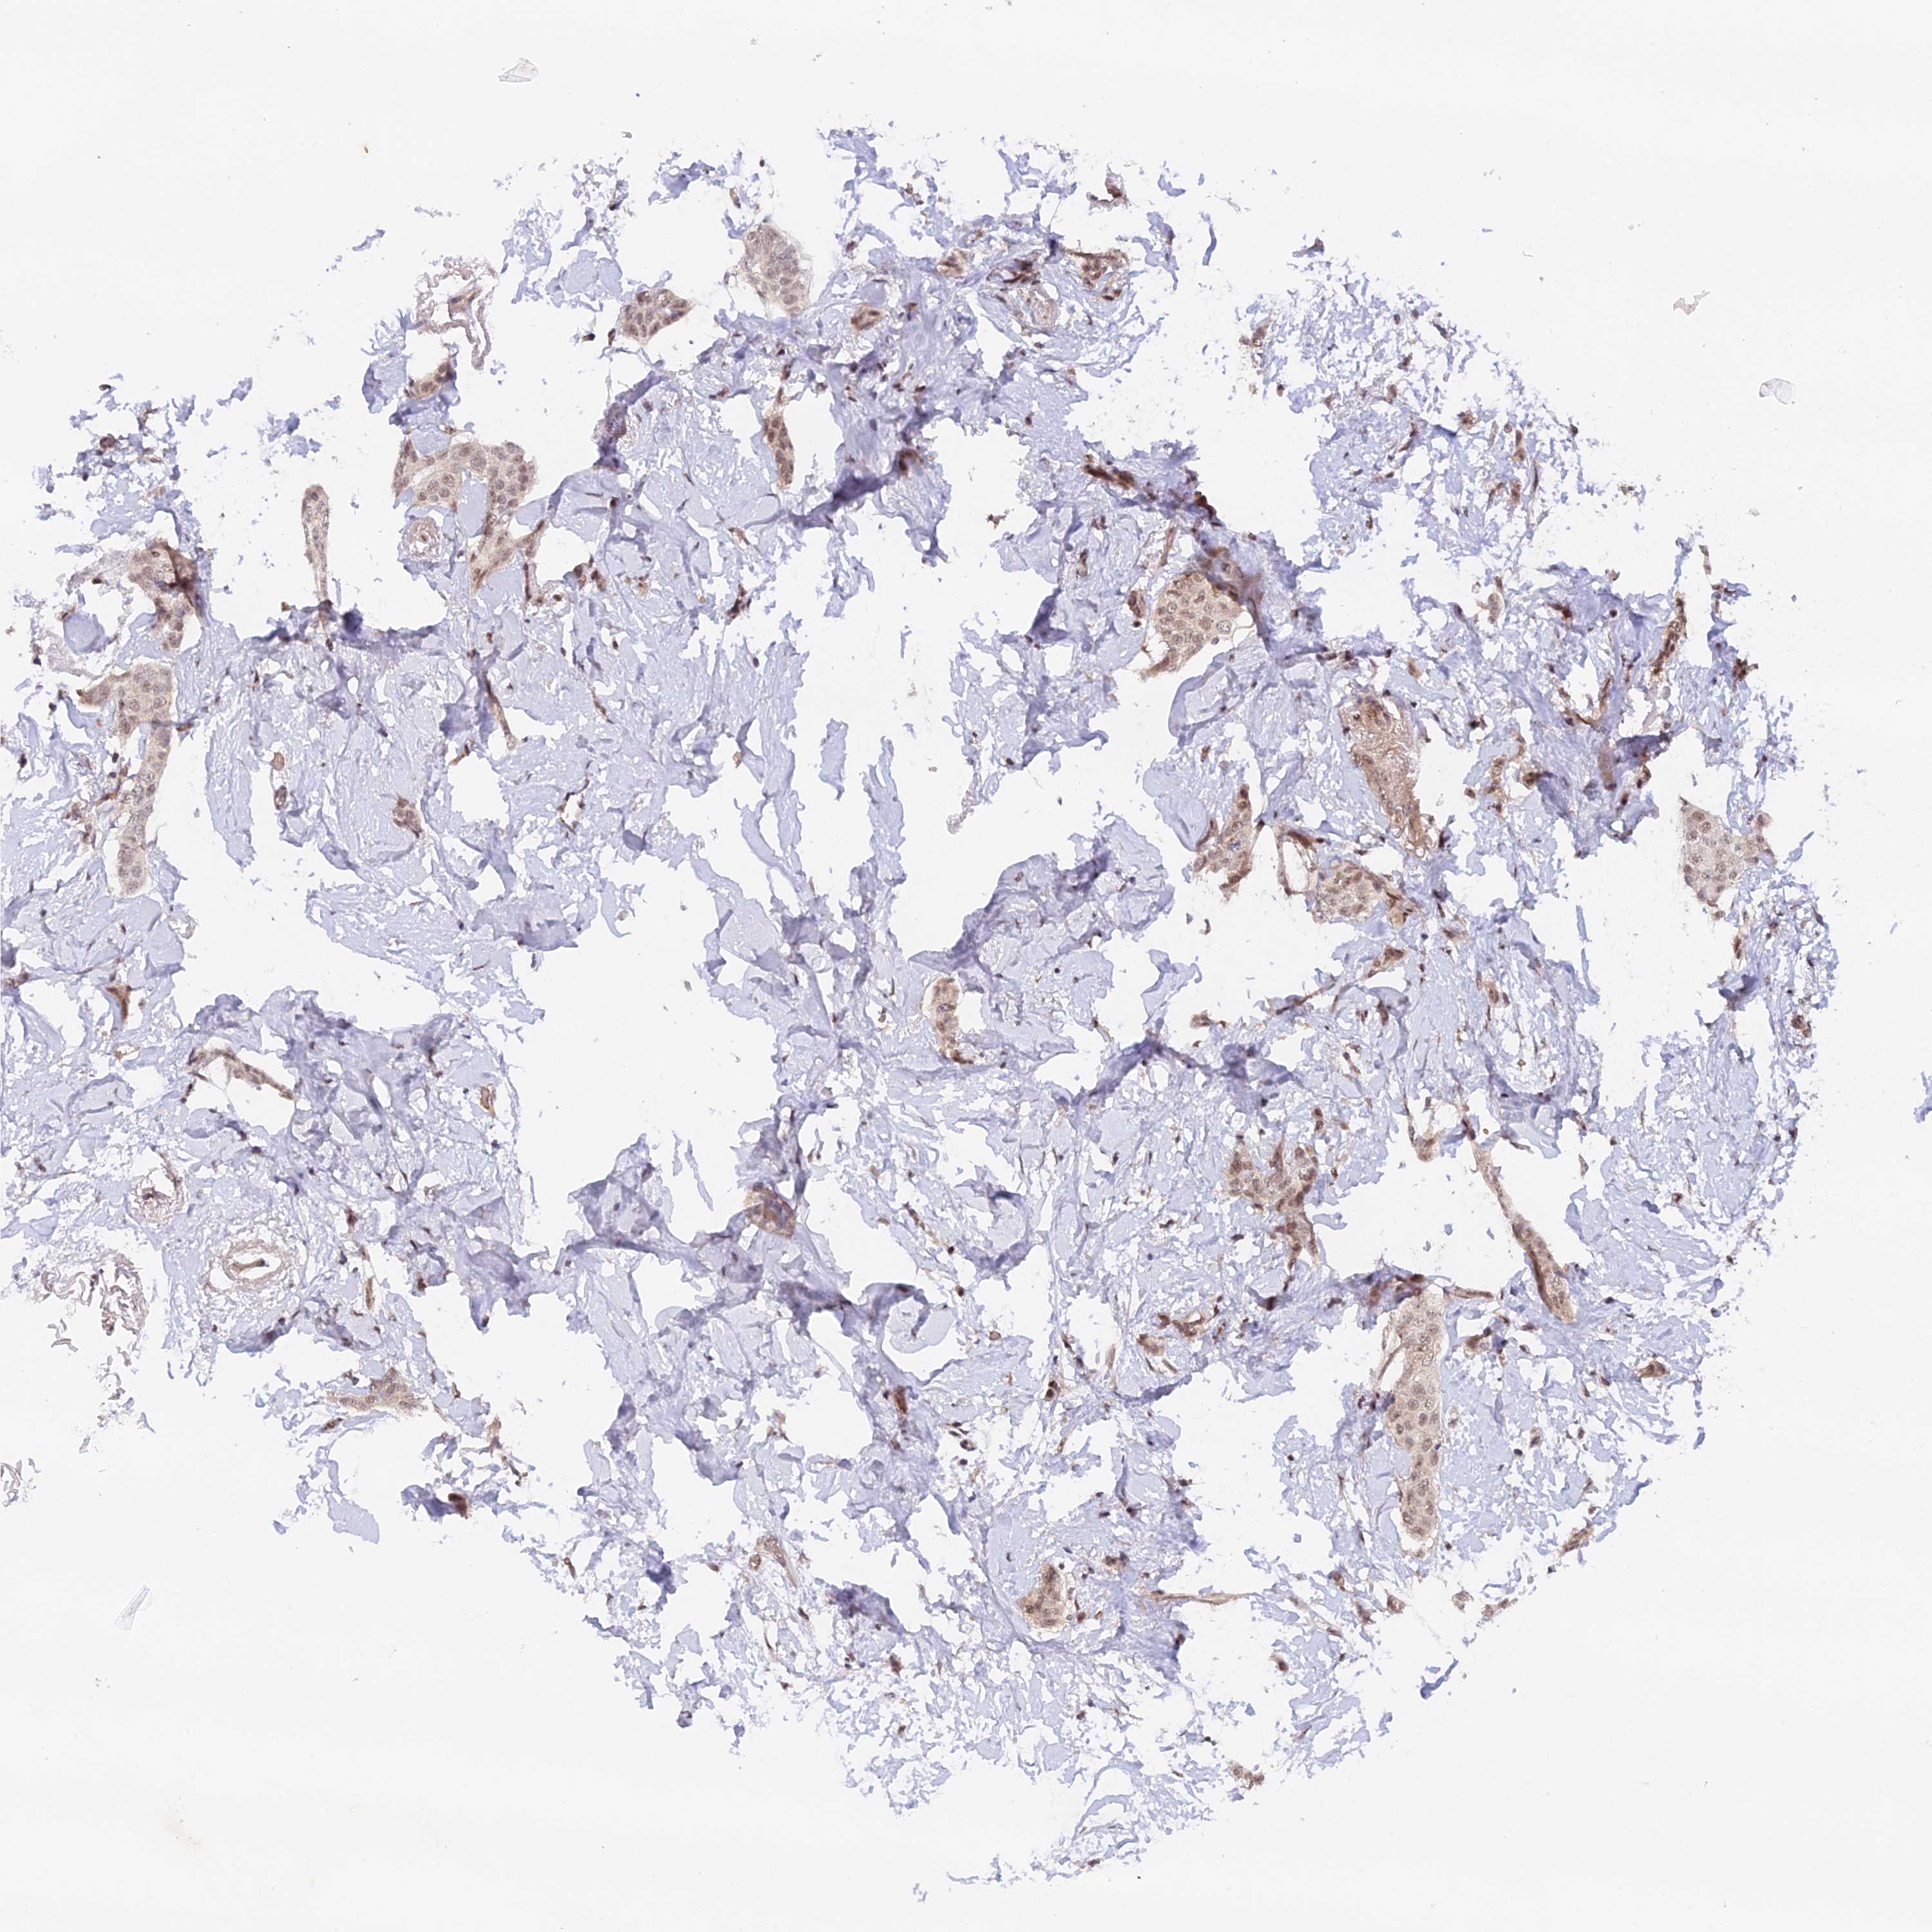

BRCA TCGA BRCA VALIDATION PROTEIN EXPRESSION

ANTIBODIES

AND

VALIDATION